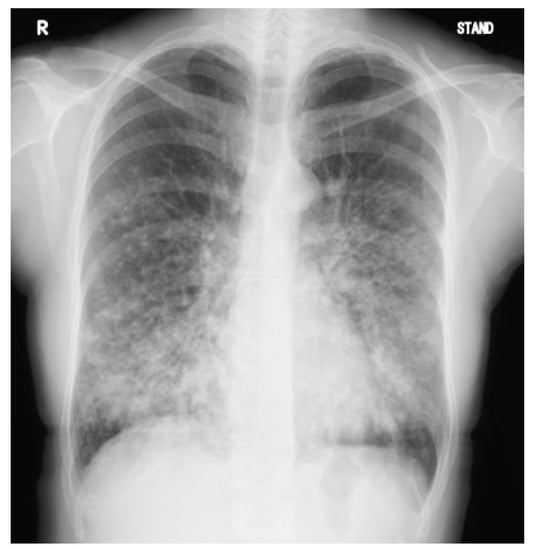

2. Case Presentation